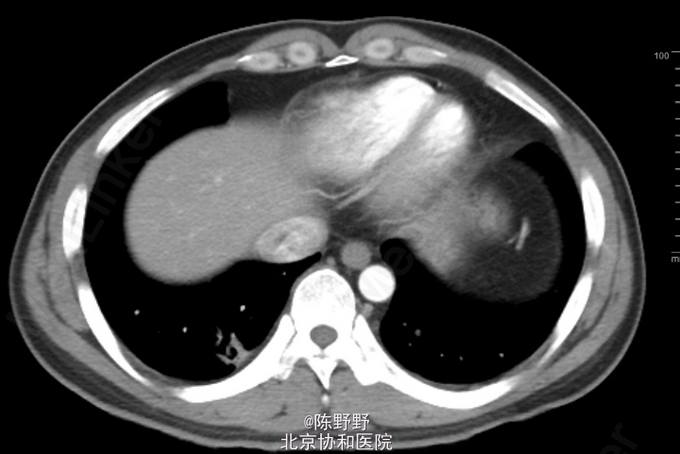

咳嗽、痰中带血丝半年

无特殊 CT提示右下肺空洞内见团状物

术前诊断考虑曲霉菌球,恶性病变不能除外 行VATS右肺下叶切除,术中切开见囊性病变内灰黑色团状病变,考虑曲霉菌球,最终病理明确诊断

术后患者恢复良好。 曲霉菌球一般继发于有囊性病变的基础上,一旦形成曲霉菌球,抗真菌药物治疗无效,需要手术治疗。术前需要CT评估,如果伴随侵袭性曲霉菌病,则需要术前应用抗真菌药物治疗控制后再行手术。若仅为曲霉菌球,需要直接手术,因为药物无效,长期还有可能导致咯血,另外,较为极端的例子是空洞型肺癌也可以合并曲霉菌球,因此一旦怀疑曲霉菌球,只要无炎症迹象,应该选择手术治疗而不是内科药物治疗